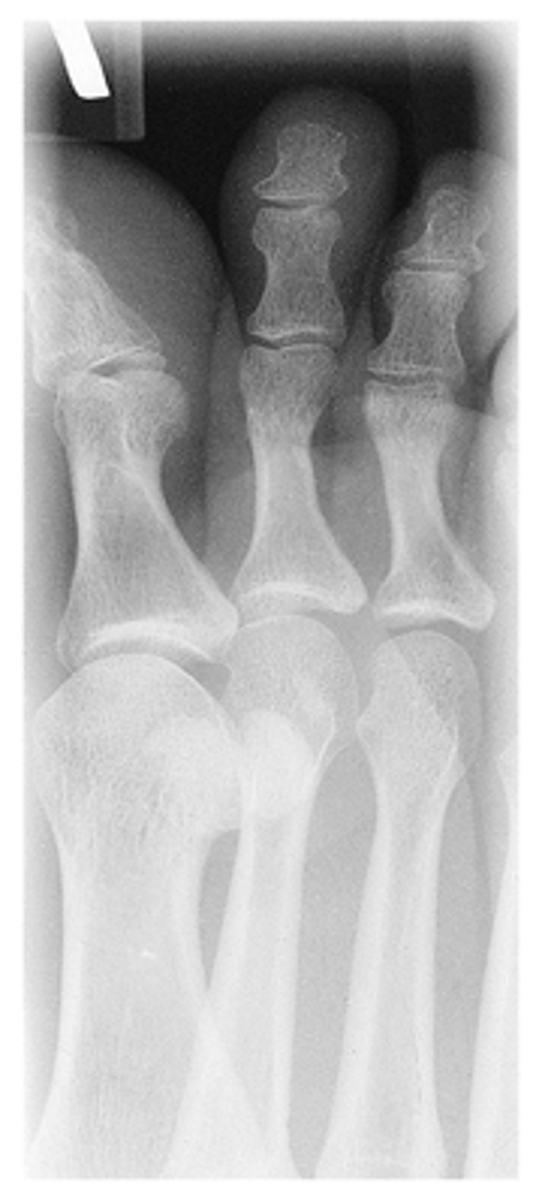

AP Oblique Medial Rotation

What projection is this?

AP Oblique Lateral Rotation

Evaluation Criteria for AP Oblique

- Digits and minimum of distal ½ of metatarsal demonstrated

- IP and MTP joints appear open

- Increased concavity on one side of shaft

- Heads of metatarsals not overlapped

- Optimal exposure factors